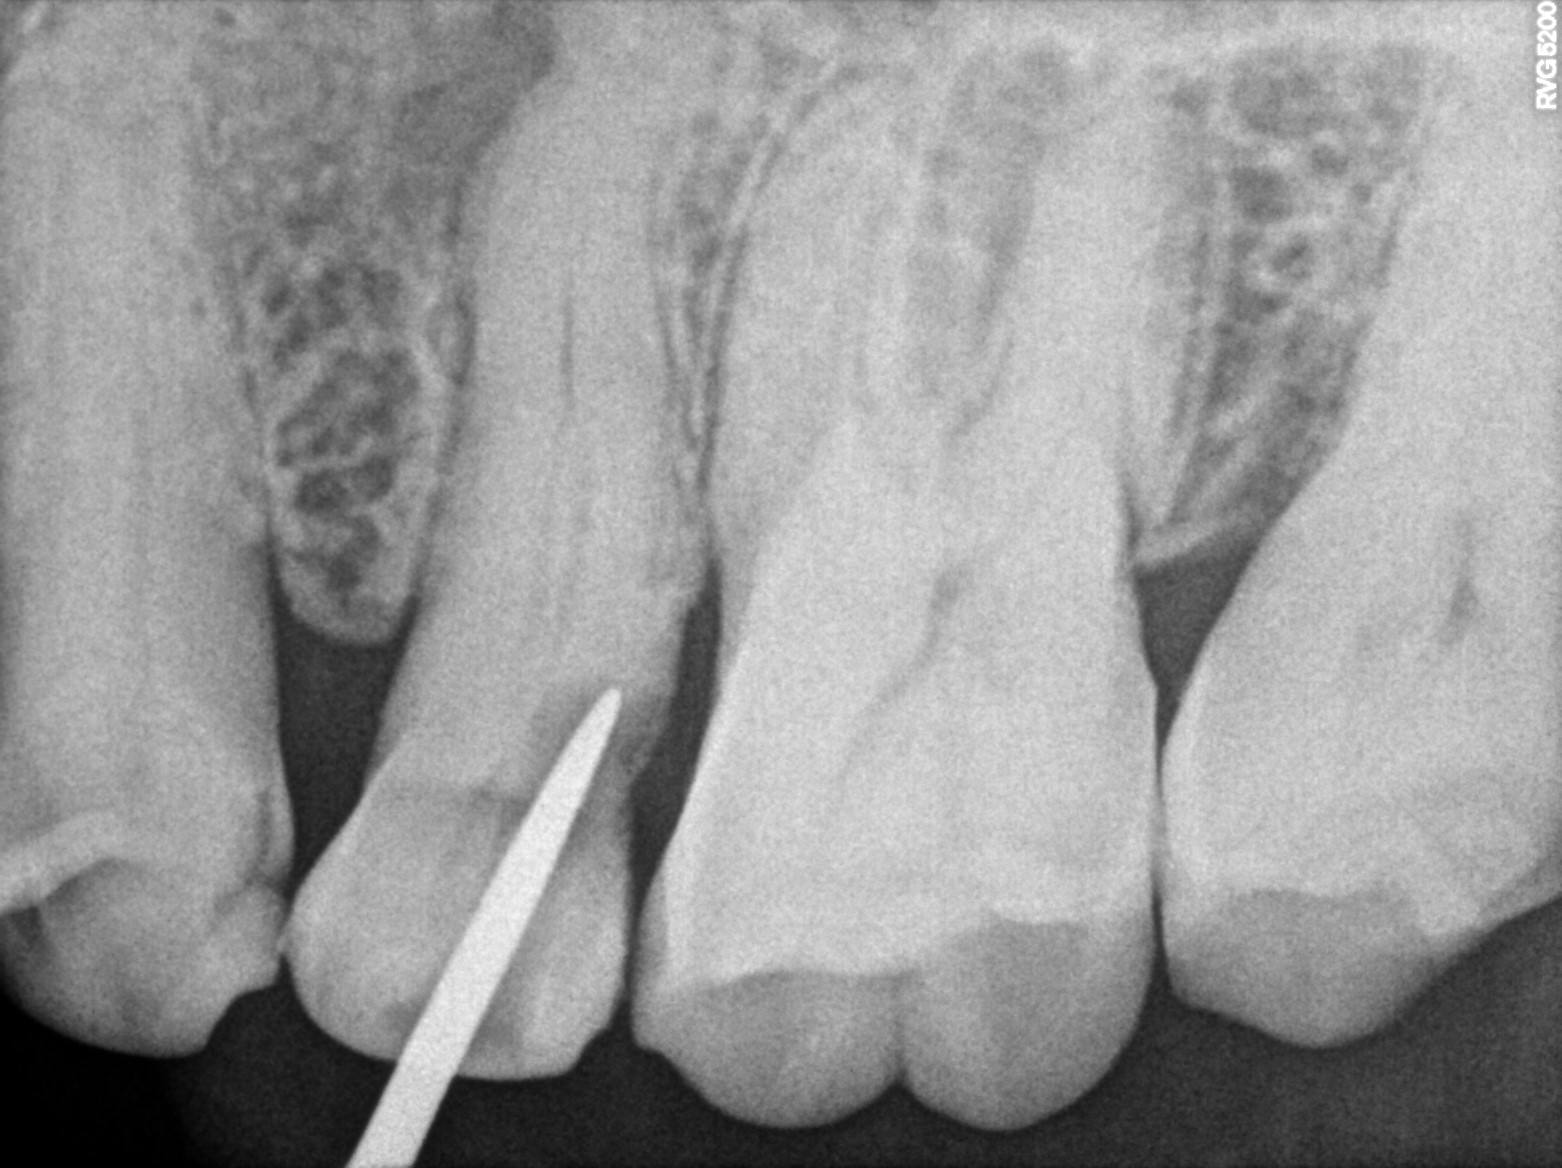

Dental Radiographs FHIR: DocumentReference · LOINC 24641-7

R60.jpg

24641-7